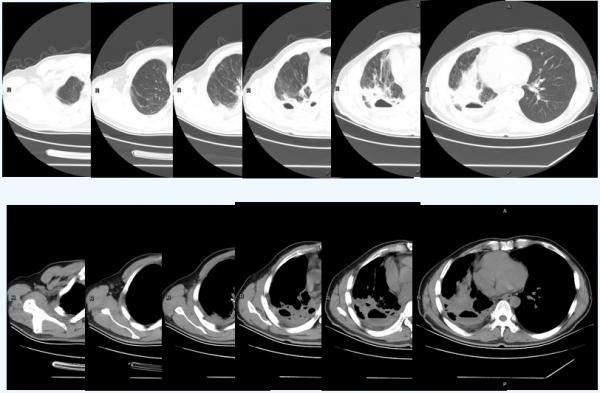

肺部CT檢查:

- 1、肺癌術後改變,吻合口周圍軟組織影,右側胸腔積液;

- 2、右肺炎症,右肺結節;

- 3、主氣管管壁增厚;

- 4、縱隔淋巴結腫大。

治療2週期後,2020-9-21複查CT:

1、肺癌術後改變,吻合口周圍不規則軟組織影,範圍較前縮小,其內新增空洞伴氣液平面形成;右側胸腔積液;

2、右肺炎症實變較前減輕,右肺結節;

3、主氣管管壁增厚較前明顯減輕,原結節灶未見顯示;

4、縱隔淋巴結腫大。

同時,患者鱗狀細胞癌相關抗原(SCCA)進行性下降。臨床療效評價為部分緩解(PR)。

治療4週期後,2020-11-18複查CT:

1、肺癌術後改變,吻合口周圍不規則軟組織影伴空洞形成,與前片比較,範圍較前縮小;其內空洞較前縮小;右側胸腔積液較前減少。

2、右肺炎症實變較前範圍縮小;右肺內結節變化不大。

3、縱隔內、右側心膈角及雙側腋下多發淋巴結輕度腫大。

4、左肺改變,考慮炎症。

從下圖可以看出,患者在免疫治療前腫瘤大面積佔位,免疫聯合治療期間快速縮瘤,後續免疫單藥維持治療帶來持續獲益。

患者於本院治療前、接受替雷利珠單抗+化療後及替雷利珠單抗單藥治療對比